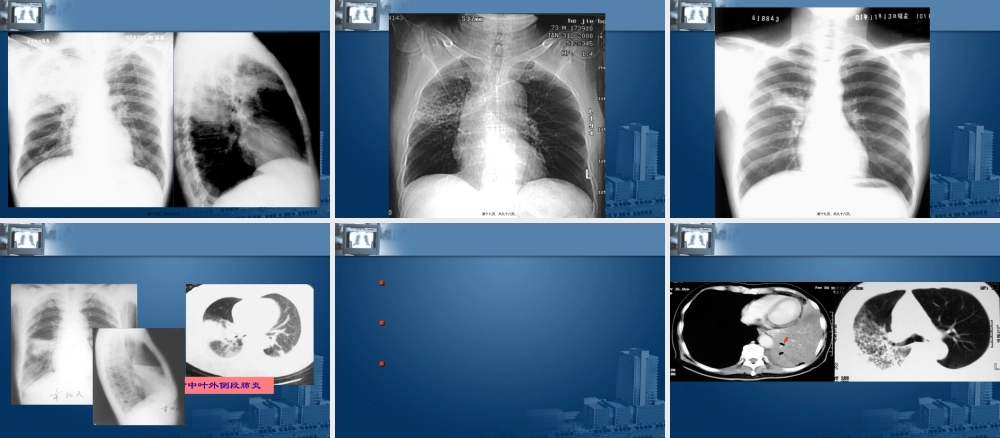

第一页,共九十八页。病理改变可有支气管粘膜炎性改变,支气管不完全阻塞以及肺部纤维化病理改变可有支气管粘膜炎性改变,支气管不完全阻塞以及肺部纤维化无特征性X线表现仅见肺纹理增多、增粗、呈网状肺透明度不同程度增高后期可有肺动脉高压,肺心病无特征性X线表现仅见肺纹理增多、增粗、呈网状肺透明度不同程度增高后期可有肺动脉高压,肺心病第二页,共九十八页。第三页,共九十八页。•肺气肿特点:–⑴两肺透光度增加,呼、吸气时相差不大,可见肺大泡,–⑵肺纹理稀疏,变细,变直–⑶桶状胸,前后径增宽,肋间隙增宽–⑷隔位置低,动度减弱–⑸侧位见胸骨后间隙增宽–⑹悬垂心第四页,共九十八页。第五页,共九十八页。肺气肿的CT表现小叶中心型肺气肿全小叶型肺气肿病理基础终末小支气管远端,位于呼吸性细支气管和肺泡管中心累及全部腺泡,主要累及下叶,与抗胰蛋白酶缺乏有关。HRCT表现肺小叶中心的点状或者线状的密度增高影,代表小叶内的动脉,充气扩张的远端气道在它周围,胸膜下1cm范围内最明显。肺实质密度广泛性减低,病变肺血管直径减小,严重时可与小叶中心性肺气肿并存并融合。按累及肺小叶的部位第六页,共九十八页。间隔旁性肺气肿(远端性腺泡气肿)瘢痕旁型病理基础主要累及远端肺泡、肺泡管和肺泡囊。被胸膜表面和小叶间隔特征性分隔肺纤维化及瘢痕病变旁异常扩张的含气腔隙HRCT表现胸膜下和支气管血管旁的低密度区,被小叶间隔分隔,有时候伴发肺大泡。几种特殊类型肺气肿肺气肿的CT表现第七页,共九十八页。多继发于支气管,肺的化脓性炎症,肺不张及肺纤维化多继发于支气管,肺的化脓性炎症,肺不张及肺纤维化平片:仅见肺纹理增多、增粗造影:支气管呈柱状或囊状扩张,管腔粗细不均,内壁呈锯齿状,各分支相互靠拢,或呈一串葡萄状平片:仅见肺纹理增多、增粗造影:支气管呈柱状或囊状扩张,管腔粗细不均,内壁呈锯齿状,各分支相互靠拢,或呈一串葡萄状第八页,共九十八页。第九页,共九十八页。支气管扩张症支气管壁的弹性组织和肌肉组织被破坏而导致的支气管不可逆性的扩张。少数为先天性,多数为后天性引起。HRCT是其最佳答案检查方法。先天性支气管扩张多呈囊状,是由支气管壁先天发育缺陷所致。后天性支气管扩张主要由支气管感染和阻塞引起第十页,共九十八页。支气管扩张诊断标准1、支气管的远端大于或等于近段2、胸壁下1CM范围内见到支气管。3、支气管内径大于伴随的肺动脉横径〔印戒征〕第十...

2、本站所有内容均由合作方或网友上传,本站不对文档的完整性、权威性及其观点立场正确性做任何保证或承诺!文档内容仅供研究参考,付费前请自行鉴别。

3、如文档内容存在违规,或者侵犯商业秘密、侵犯著作权等,请点击“违规举报”。

碎片内容

蜗牛文库的最新文档